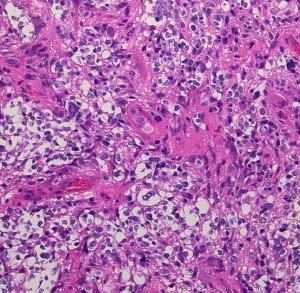

病理組織像を見たら次に遺伝子診断をして確定病理診断とします

glioblastomahe2

これは普通の病理組織診断です。これだけで膠芽腫という診断はつきます,

2022年時点での病理学での定義と臨床

• 組織学的には,びまん性の星細胞系グリオーマであり,血管内皮増生と壊死が特徴です

• IDHとH3遺伝子には変異がありません 野生型 wild typeといいます

• 特異的な遺伝子異常として,TERT promoter mutation, EGFR gene amplification and/or a +7/–10 cytogenetic signatureがみられます

• 組織診断で低悪性度びまん性星細胞腫でも,IDH wild typeでかつ,TERT promoter mutation, EGFR gene amplification, +7/–10 copy number changes のどれか一つがあれば,膠芽腫グレード4と診断します

下の病理写真は,ある患者さんから私に送られたものです。20代で前頭葉の膠芽腫になってから21年経って生存しておられるということです。2度の開頭術と放射線治療と化学療法(複数回)を受けておられます。患者さんに病理診断が間違っているのではないかと返事をしたら,下にある画像を送ってくださいました。病理診断は,一見したところは多形膠芽腫 グリブラに間違いありませんでした。でも,ーーー

(下の画像は患者さんの許可を得て掲載させていただきました)

bizarre! 異様な細胞が混在しています。核多型が目立ち,多核巨細胞も混じる典型的な膠芽腫の像です。下の左の画像は血管内皮の肥厚 endovascular proliferationがあり,下の右のKi-67染色では核濃染像が多く核分裂能が高いことを示します。しかし,——